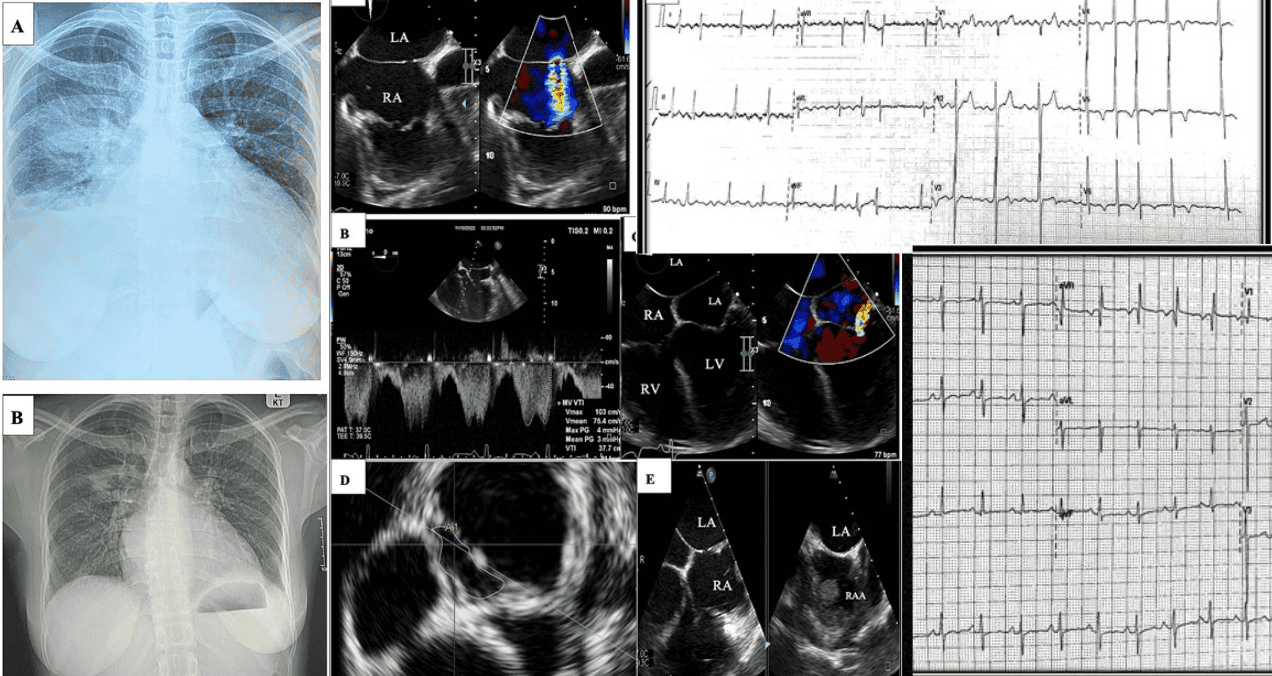

La radiografía de tórax inicial confirmó la presencia de congestión pulmonar, mostrando una silueta cardíaca agrandada, arterias pulmonares prominentes, derrame pleural derecho y consolidación en el lóbulo inferior derecho.

El electrocardiograma de 12 derivaciones mostró signos de agrandamiento de la aurícula izquierda, hipertrofia y distensión del ventrículo derecho, además de insuficiencia tricuspídea.

La ecocardiografía transtorácica (ETT) demostró un agrandamiento de la aurícula derecha e hipertrofia del ventrículo derecho, con un espesor de la pared libre de 7 mm. Se identificó una insuficiencia tricuspídea de moderada a grave, y la presión sistólica de la arteria pulmonar estaba significativamente elevada, estimada en 100 mmHg.

La fracción de eyección del ventrículo izquierdo estaba gravemente reducida al 20%. Una ecocardiografía transesofágica (ETE) más detallada reveló hallazgos críticos: una pequeña comunicación interauricular (CIA) con un área 3D de 0,42 cm² que provocaba un cortocircuito de izquierda a derecha, y una membrana en la aurícula izquierda, por encima de la válvula mitral, consistente con un cor triatriatum.

Esta membrana presentaba un defecto que medía 1,3 cm² en la reconstrucción 3D, con un gradiente medio transorificio de 3 mmHg, el cual probablemente fue subestimado debido al estado de bajo gasto cardíaco. Adicionalmente, se observó una insuficiencia mitral funcional excéntrica de moderada a grave y se detectó un gran trombo en la orejuela de la aurícula derecha.

La paciente fue reevaluada en consulta externa a los tres y seis meses posteriores. Reportó una mejoría subjetiva de sus síntomas, la cual fue corroborada por la exploración física y una nueva radiografía de tórax que mostró una mejoría significativa del edema pulmonar. La fracción de eyección del ventrículo izquierdo mejoró hasta el 34%.

No obstante, en el seguimiento se documentó la nueva aparición de un aleteo auricular persistente con bloqueo de conducción variable. Esta nueva arritmia se manejó optimizando la dosificación de la terapia con betabloqueantes para lograr un control adecuado de la frecuencia cardíaca.